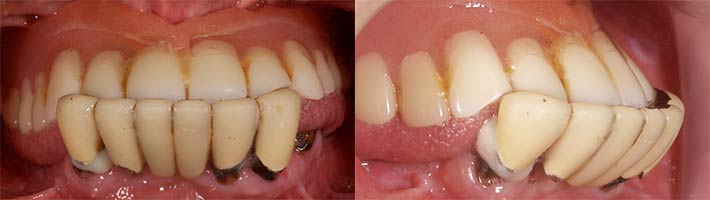

術前の診査診断

術前写真

上顎:残存歯なし.安定剤を付け 総義歯をなんとか使用している

下顎:両側臼歯部は欠損. 前歯部はグラグラで残す事が出来ない